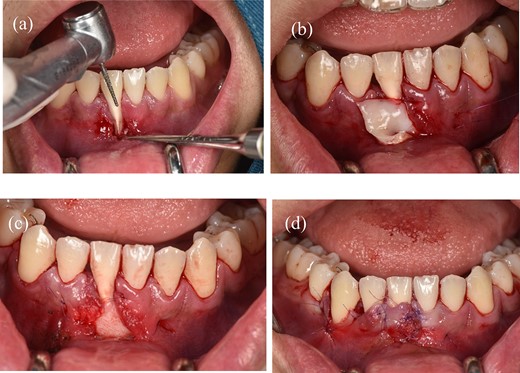

Before surgery: scaled the lower incisors and endodontic treatment. After 2 weeks, the inflammation of the gingival had decreased and we can start the gingival graft treatment and the surgical procedure is depicted below (Fig. 3). Local anesthesia then followed by meticulous preparation of the tooth surface using a high-speed handpiece. To prepare the root surface, a 24% ethylenediaminetetraacetic acid (EDTA) gel was used. To obtain an epithelialized connective tissue graft (CTG), tissue was harvested from the hard palate in the area from first premolar to first molar. The graft was carefully shaped and sized based on the specific measurements of the gingival recession defect. A specialized 15C blade was utilized for this precise procedure. Subsequently, a thin layer of epithelial tissue, ~0.5–1 mm in thickness, was eliminated from the graft using a high-speed handpiece and 2 mm round diamond bur, except for the specified epithelial section as illustrated in (Fig. 2a). A piece of connective tissue in size 13 × 13 × 1.5 mm was harvested to adequately cover the entire tooth root (Fig. 2b and c). Afterward, Emdogain was applied to the complete root surface, starting from the most apical bone level to maximize the therapeutic potential of Emdogain in facilitating tissue regeneration and promoting periodontal healing. On the right side, where gingival recession was observed on the teeth, a flap with varying thickness was raised. This flap featured a split-thickness technique in the papillae and vestibular sulcus, while maintaining full thickness at the center. An incision was created to alleviate tension, specifically at a location distant to the right canine. Through the sulcular access on the left side of tooth 41, the graft was inserted into the tunnel, and the epithelial segment of the graft was positioned over the exposed root. Subsequently, the graft sites on both the left and right central incisors were secured using 6–0 monofilament sutures. Finally, the gingival flap was repositioned to cover the entire connective tissue area (Fig. 4). Subsequent assessments and recording of the healing process were performed at intervals of 3 weeks, 2 months, 6 months, and 1 year through reevaluation and imaging (Figs 5 and 6).

(a) Preparing the tooth surface using a high-speed handpiece. (b) Unilateral tunneling technique. (c) Stabilize the connective tissue graft. (d) Rotate the flap and reposition the gingival margin.